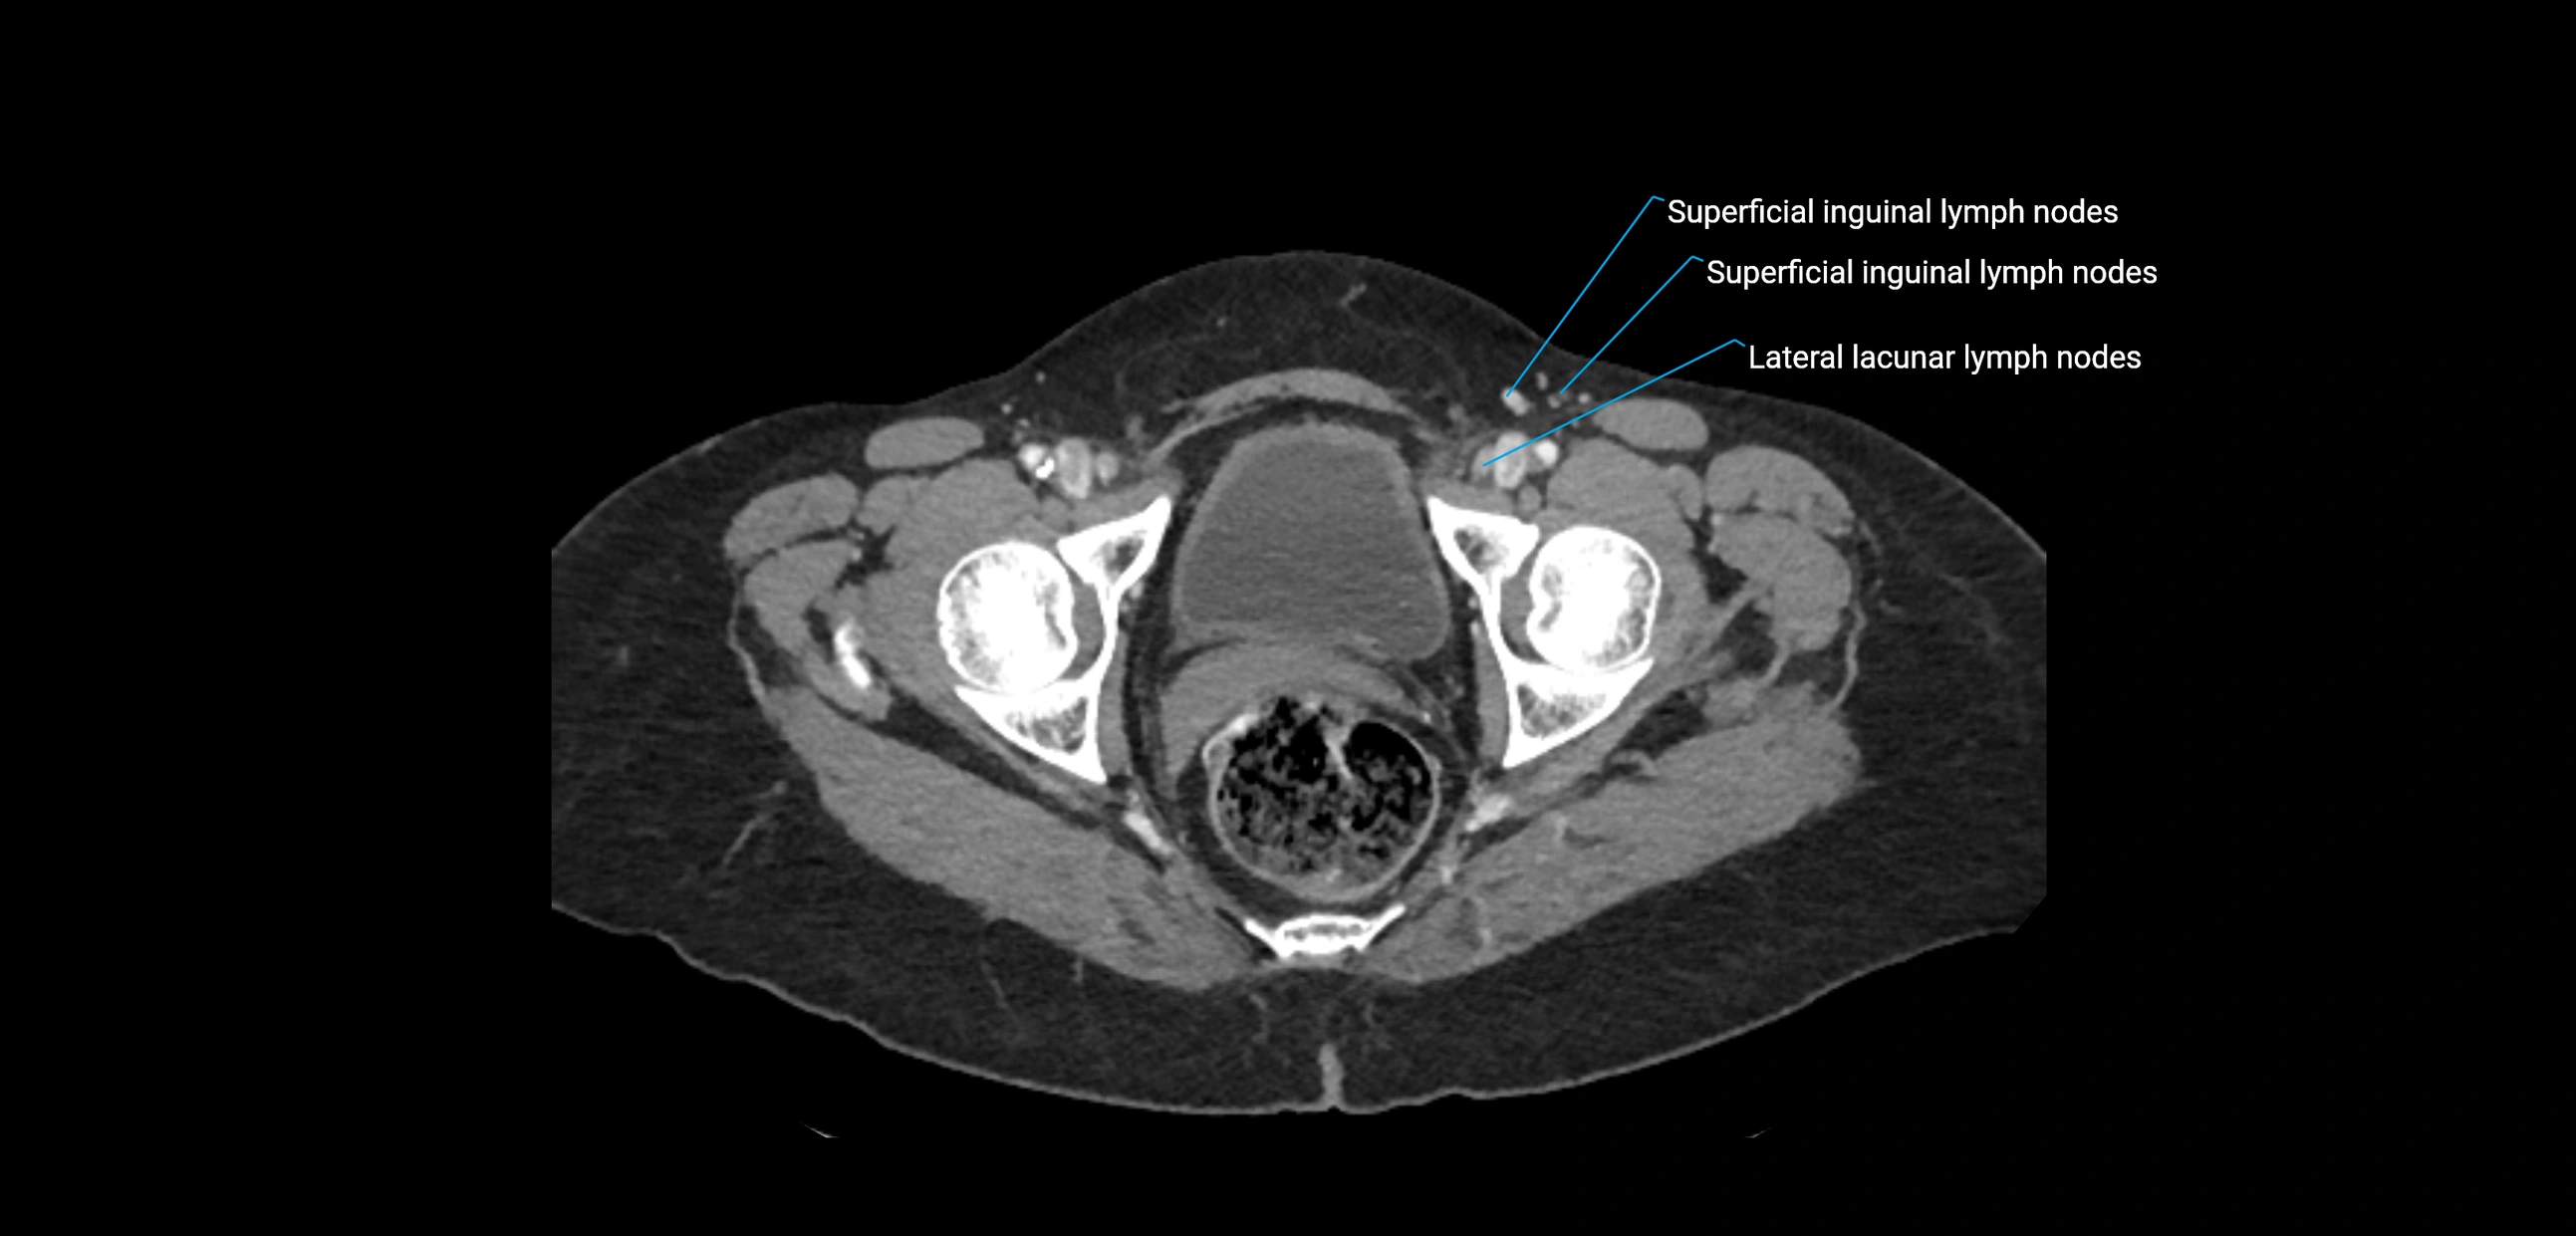

CT Appearance

CT Pre-Contrast:

• Nodes appear as soft-tissue density nodules adjacent to the aorta and IVC

• Calcification may be seen in chronic infections (e.g., tuberculosis)

CT Post-Contrast:

• Normal nodes enhance homogeneously

• Malignant nodes may show heterogeneous enhancement, central necrosis, or conglomerate formation

• Size >1 cm short axis is suspicious, though morphology and distribution are equally important